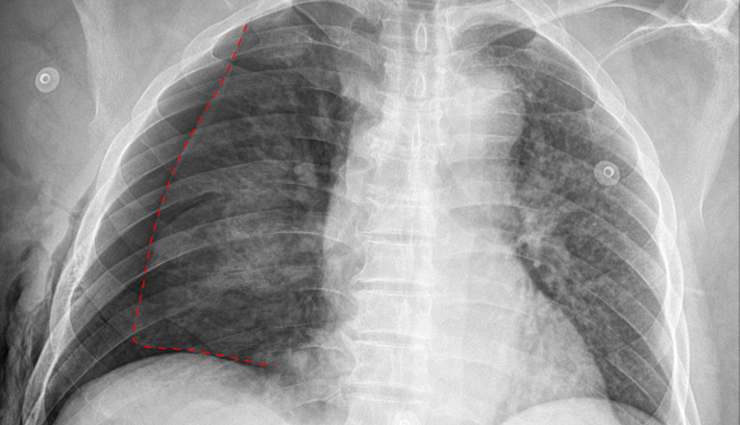

Pneumothorax is a medical condition characterized by the presence of air or gas in the pleural cavity, the space between the lungs and the chest wall. Normally, this space is filled with a small amount of fluid that helps the lungs expand and contract smoothly during breathing. When air enters this space, it can cause the lung to collapse partially or fully, depending on the amount of air present.

Symptoms of pneumothorax can include sudden chest pain (often sharp and on one side), shortness of breath, rapid breathing, and sometimes a bluish discoloration of the skin due to lack of oxygen. Diagnosis is typically made through a physical exam, imaging tests like chest X-ray or CT scan, and sometimes by measuring oxygen levels in the blood.

Treatment depends on the severity of the pneumothorax. Small pneumothoraces may resolve on their own, but larger or symptomatic cases may require intervention. Treatment options include observation, chest tube insertion to remove the air and allow the lung to re-expand, and occasionally surgery to repair the lung if the condition is recurrent or severe.